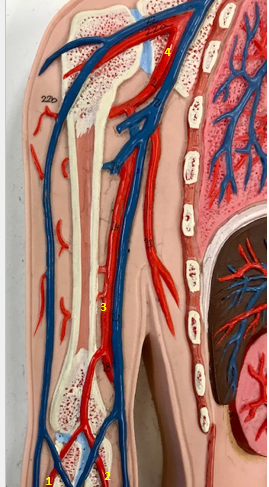

Tunica intima

Name the blue arrow

Lines lumen and release vasoactive chemicals

Function of tunica intima

Venous valves

Name the pink arrow

Prevent backflow of blood

Function of venous valves

Tunica media

Name green arrow

Vasoconstriction and vasodilation

Function of tunica media

Tunica externa

Name the purple arrow

Anchor and bind vessel

Function of tunica externa